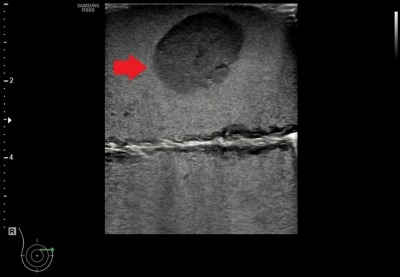

| ที่มา ข้อมูลเบื้องต้น ความสำคัญของปัญหา มะเร็งเต้านมเป็นมะเร็งที่พบบ่อยที่สุดในผู้หญิงไทยและมีแนวโน้มเพิ่มขึ้นต่อเนื่อง การตรวจคัดกรองจึงจำเป็น เพราะหากพบเร็วจะรักษาได้ทันและมีโอกาสหายสูง การใช้แมมโมแกรมร่วมกับอัลตราซาวด์ช่วยเพิ่มโอกาสพบรอยโรค ซึ่งต้องยืนยันด้วยการตรวจชิ้นเนื้อโดยใช้เครื่องมือทางรังสีช่วยนำเข็ม เนื่องจากรอยโรคมักคลำไม่พบ การฝึกใช้เครื่องมืออย่างมีประสิทธิภาพช่วยเพิ่มทักษะให้บุคลากรทางการแพทย์ จึงมีการพัฒนาเต้านมจำลองสำหรับฝึกนำเข็มอัลตราซาวด์เก็บชิ้นเนื้อ ซึ่งควรมีลักษณะเหมือนเต้านมจริง เห็นก้อนและเข็มชัด ใช้ซ้ำได้ ไม่ทิ้งรอยเข็ม และมีราคาที่เหมาะสม เทคโนโลยีทางด้านวัสดุเลียนแบบเนื้อเยื่อที่สามารถซ่อมแซมตัวเองได้ที่พัฒนามาใช้ในการทำเต้านมจำลองนี้ ได้ถูกพัฒนาต่อยอดร่วมกับเทคนิคการขึ้นรูป จึงสามารถพัฒนาอวัยวะอื่น ๆ เพื่อฝึกทำหัตถการ เช่น ผิวหนังเทียมในการฝึกเย็บ หรือตับที่สามารถแสดงภาพอัลตราซาวด์โดยที่มีรายละเอียดของเส้นเลือดหรือท่อน้ำดีเพื่อใช้ฝึกวินิจฉัย เป็นต้น |

| สรุปเทคโนโลยี • ให้ภาพอัลตราซาวด์ที่เห็นก้อนเนื้อชนิดต่าง ๆ ชัดเจน • ให้ภาพอัลตราซาวด์ของเข็มเจาะชัดเจน • สามารถใช้ซ้ำเนื่องจากวัสดุมีคุณสมบัติซ่อมแซมตัวเองได้ • สามารถต่อยอดไปสู่การพัฒนาอวัยวะอื่น ๆ เพื่อให้แพทย์ได้ฝึกทำหัตถการ |